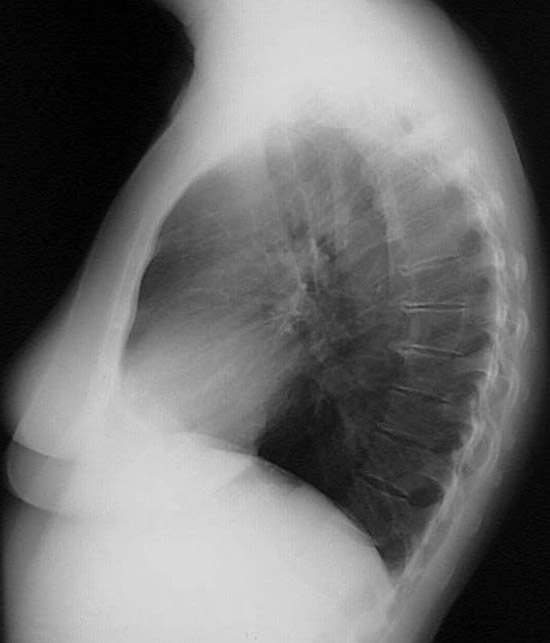

This is a normal lateral chest radiograph in a female who has slight upper thoracic spondylosis.